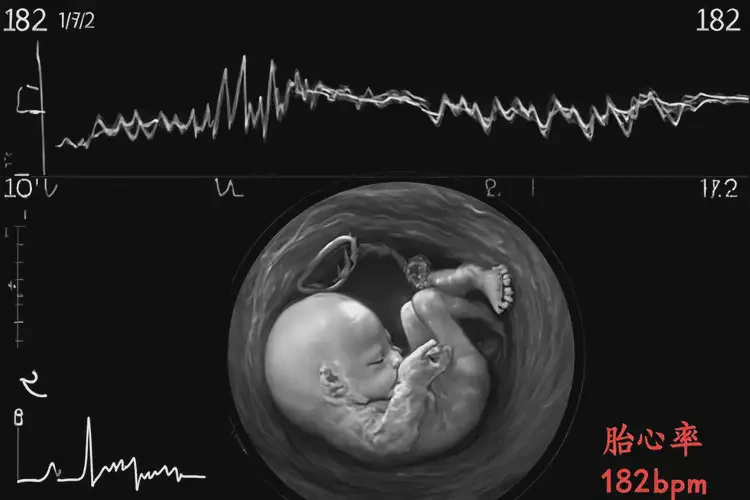

胎心率182次/分鐘

孕32周時,胎心率達(dá)到182次/分鐘可能引發(fā)擔(dān)憂。通常,胎兒的正常心率范圍在120-160次/分鐘之間。胎心率的短暫升高可能由多種因素引起,包括胎兒活動、孕婦情緒波動或外界刺激等。以下是對這一現(xiàn)象的詳細(xì)解析:

孕32周胎心率182怎么回事(圖1)